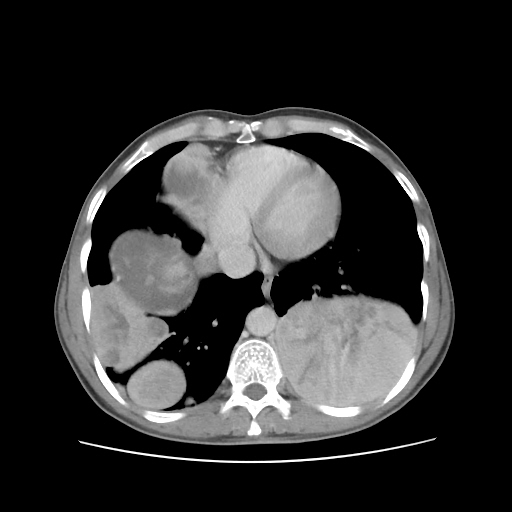

HRCT was done on 22 feb 2016